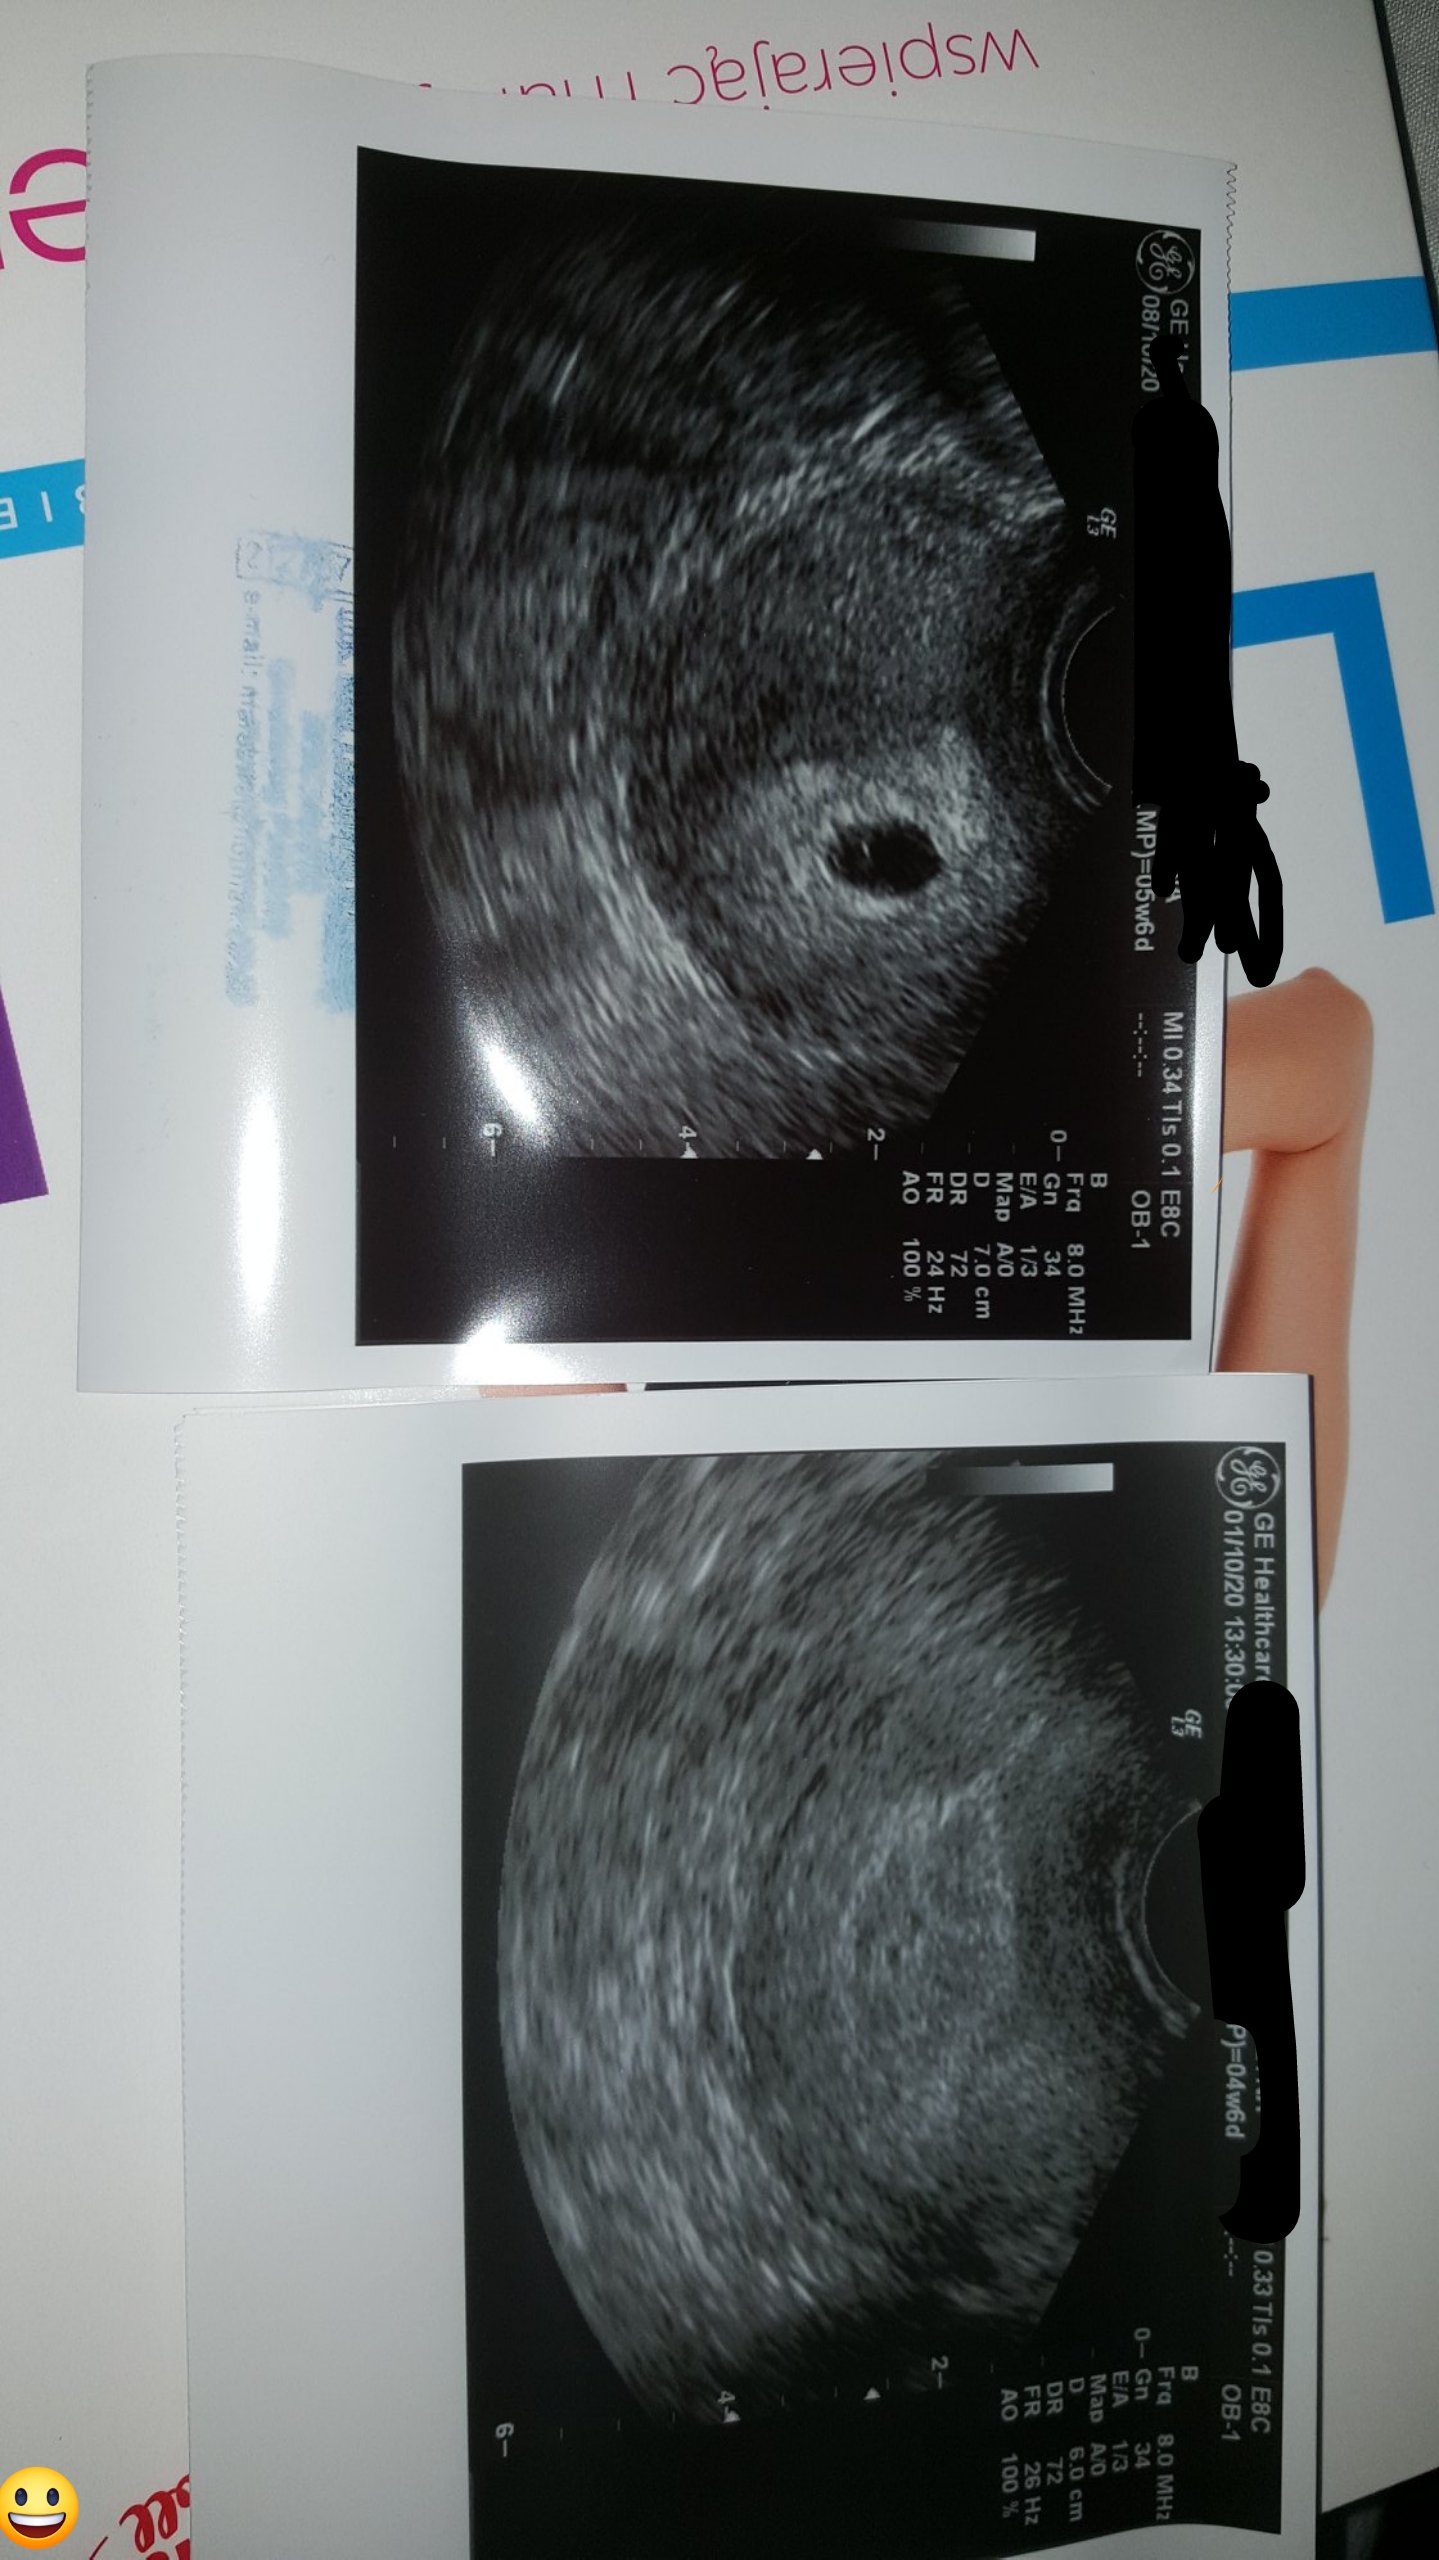

Ja dzien po becie 670 bylam na usg i był taki obraz jak ten po prawej

Załączniki

• USER_SCOPED_TEMP_DATA_orca-image-1602399771406_6720951770809261460.jpeg